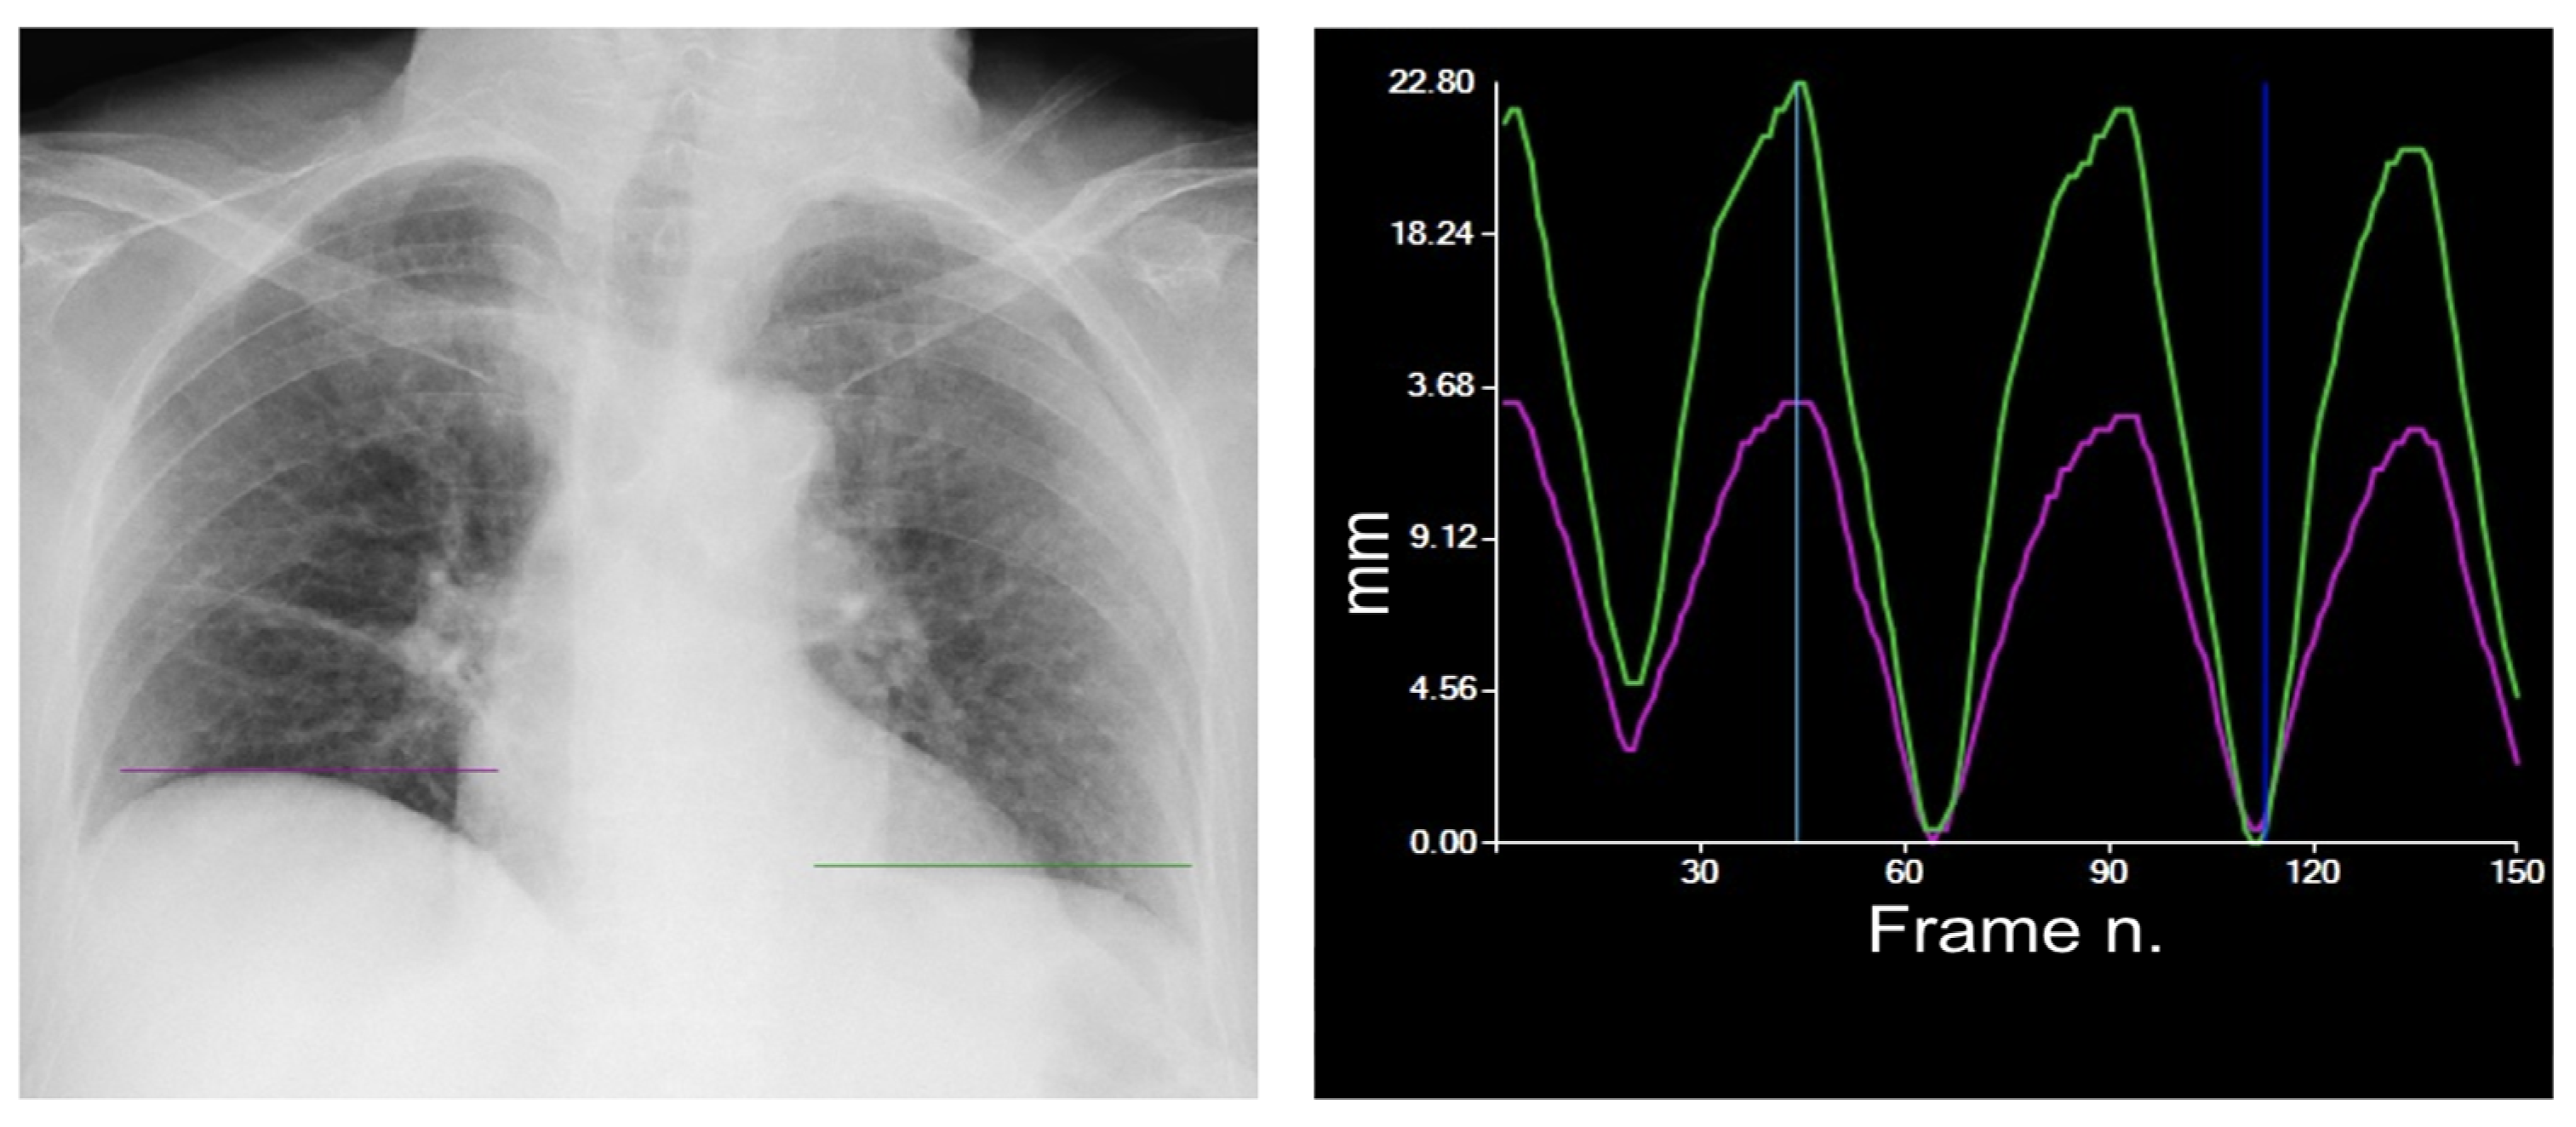

| DM-mode | Tracking diaphragm motion. Automatic calculation of the lung area and the relative changing rate (%). | Tracking of diaphragmatic domes represented in a motion–time graph. Area detection through an edge detection method in the post processing phase. | Diagnosis of diaphragm motion impairment and palsy. Automatic calculation of the respiratory rate. Analysis of lung dynamics in patients with restrictive/obstructive diseases. Follow-up of patients in pulmonary rehabilitation. |